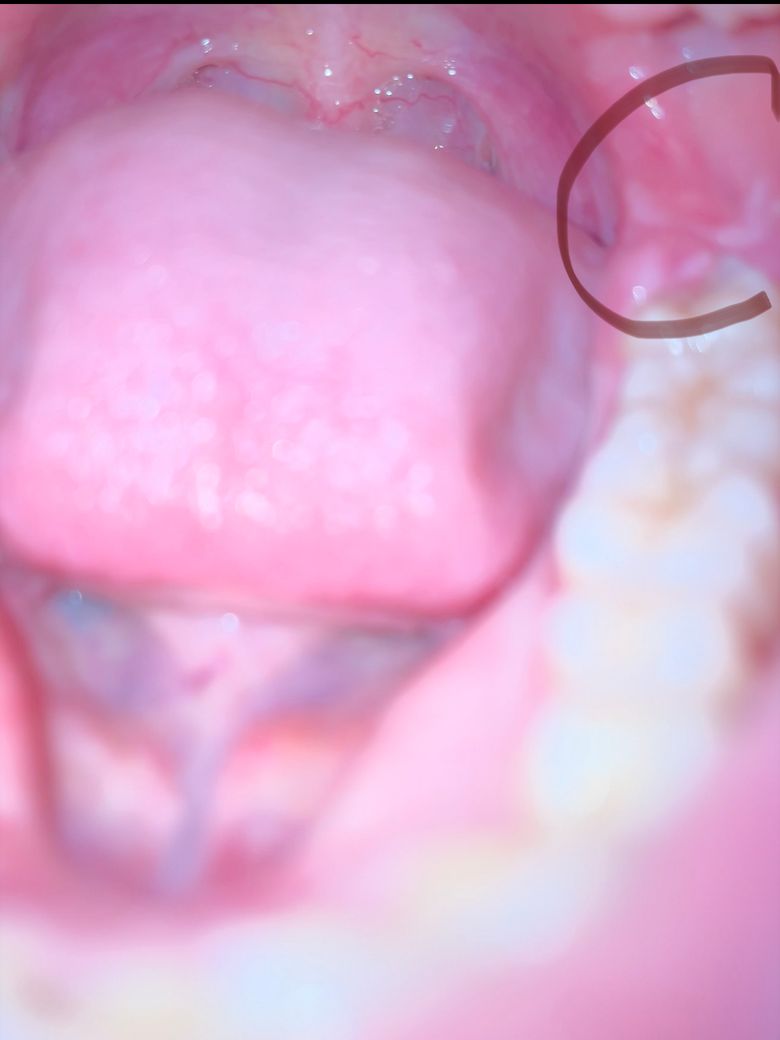

(사진有) 잇몸/입안이 부은 느낌이 있는데 뭐가 문제인가요?

오늘은 아니지만 어제 내내 약간의 통증이 있었고 부어오른 느낌이 확실이 느껴져서 신경쓰였습니다. 지금은 아무런 통증 없이 간질간질한 느낌이 듭니다. 오늘 보니 사랑니쪽에 이렇게 되어 있던데 사랑니를 뽑아야 하는걸까요? 사랑니 뒤쪽에 있는 하얀 물집같은 것은(건드려보면 살 같기도 합니다)무엇인가요? 기왕이면 사랑니를 뽑고싶지 않은데 걱정입니다… 나이는 21입니다

• 1번 째 사진

사랑니 뒤쪽잇몸이 위쪽치아에 씹혀서 그런거 같습니다. 많이 불편하시면 사랑니를 빼야 해결되실꺼 같습니다.

사랑니가 입안에 염증을 유발하는 경우 우선적으로 발치를 하길 권하기에 빠른시일내에 치과에 방문하여 진료를 받고 발치를 하길 권합니다.